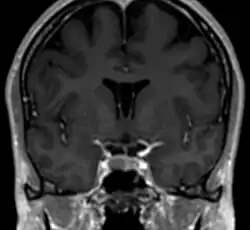

Le septum pellucidum, est une membrane verticale, fine, triangulaire séparant les cornes antérieures des 2 ventricules latéraux du cerveau, passant du corps calleux jusqu'au fornix.

Le septum pellucidum est situé sur la ligne médiane du cerveau, entre les deux hémisphères cérébraux. Il est attaché en haut au corps calleux, l'ensemble des fibres nerveuses qui connectent les 2 hémisphères. En arrière il est en rapport avec la partie antérieure du fornix, et de part et d'autre on trouve la face médiane des deux ventricules latéraux.

Le septum pellucidum est formé de 2 couches ou laminae, constituées, à la fois, de la substance blanche et de la substance grise[1]. Durant le développement fœtal, il existe un espace entre les deux laminae appelé « Cavum septum pallidum », qui va disparaître dans 90 % des cas au cours de l'enfance[2],[3]. Ce cavum (à ne pas confondre avec le cavum) est appelé parfois le 5e ventricule, cependant ce terme a perdu de son importance du fait qu'il n'existe pas de communication avec le reste du système ventriculaire[4],[5].